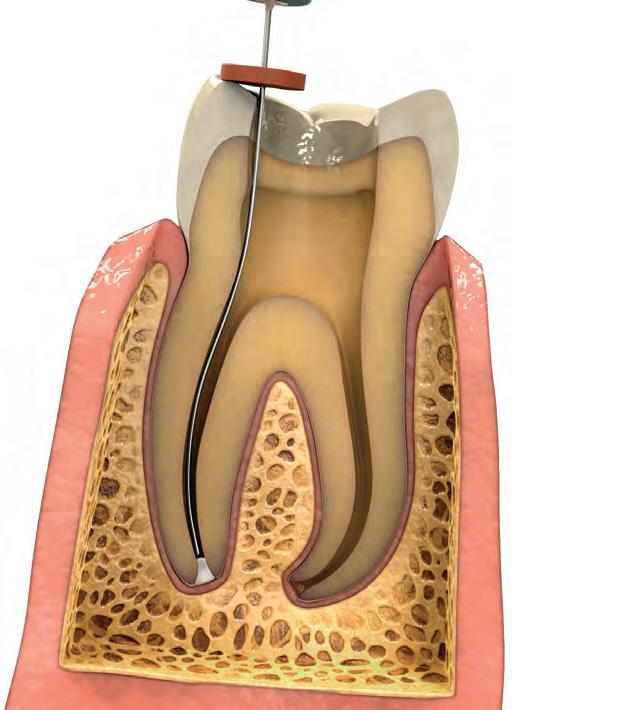

ENDODONTICS • 117–132

Mineral Trioxide Aggregate Repair

Cement

Canal Sealer

Resin-Coated Gutta Percha

File Lubricants

Calcium Hydroxide Paste

Citric Acid

Endodontic Tips Posts and Drills

Light-cured temporary resin